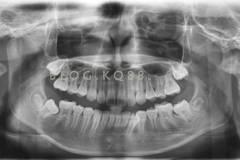

下面這個(gè)小患者就存在需早期矯正的問題。通過早期矯正,在不長(zhǎng)的時(shí)間內(nèi)就達(dá)到極為明顯的療效。她的情況如果等到牙齒替換完畢后再解決,矯治的難度則會(huì)非常大。

早期矯正之前